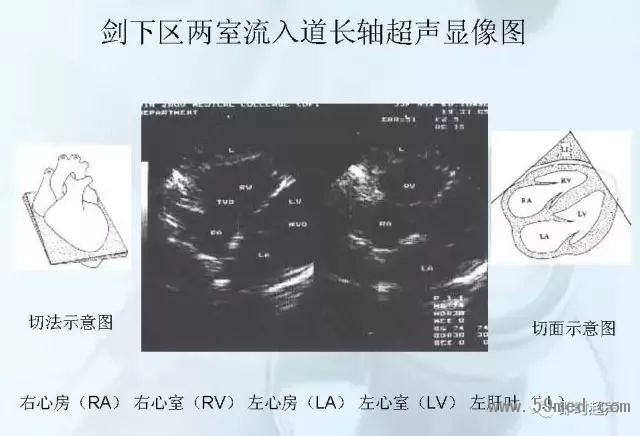

![]() ![]() ![]() ![]() ![]() ![]() ![]() ![]() ![]() ![]() ![]() ![]() ![]() ![]() ![]() ![]() ![]() ![]() ![]() ![]() ![]() ![]() ![]() ![]() ![]() ![]() ![]() ![]() ![]() ![]() ![]() ![]() ![]() ![]() ![]() ![]() ![]() 【注:本文來源于即時超聲,版權(quán)歸原作者所有,如有侵權(quán) 請聯(lián)系 速刪】 =========================== 【閱精彩*悅分享】隨手點擊轉(zhuǎn)至朋友圈,與大家一起分享精彩資訊!當(dāng)然您也可以通過以下方式找到我,與您共同分享藍(lán)韻影像超聲的更多精彩!微信號:landultrasound 電話:+86-0755-66869896 24小時客服熱線:400-888-6452